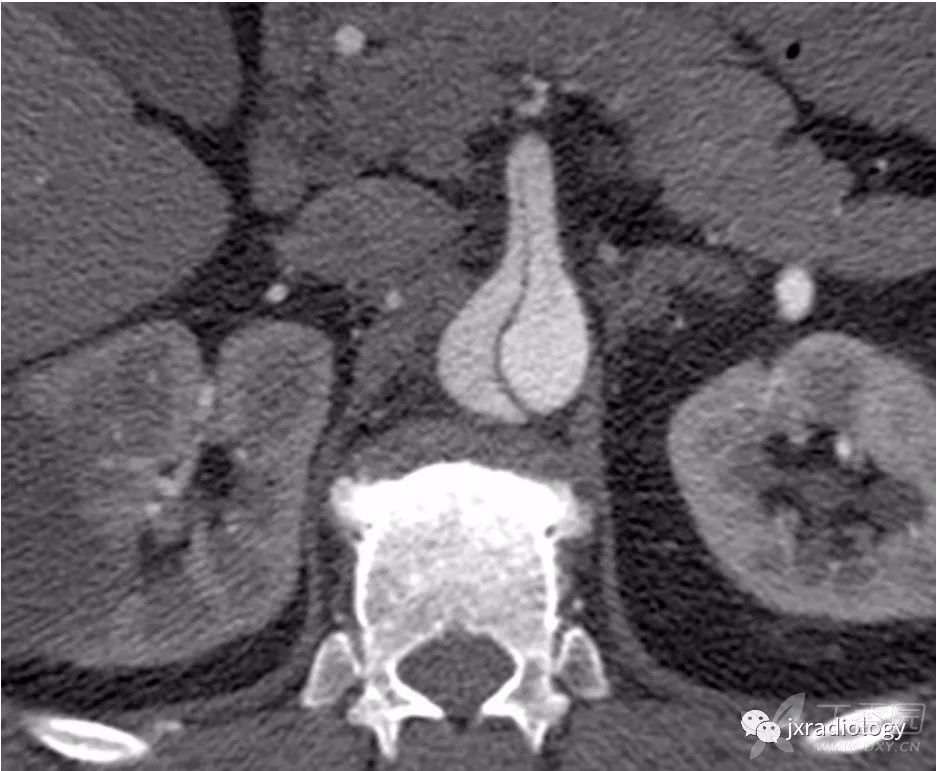

由于增强扫描可能使其显示不清,所以平扫CT是必需的。CT平扫可能会在主动脉壁上显示新月形的高密度影,主动脉腔受压改变( 图12 )。

图12:平扫CT显示主动脉左壁(a图星号)的高密度应,没有轮廓变形。(b)增强后没有造影剂渗漏,结果符合壁内血肿的诊断。